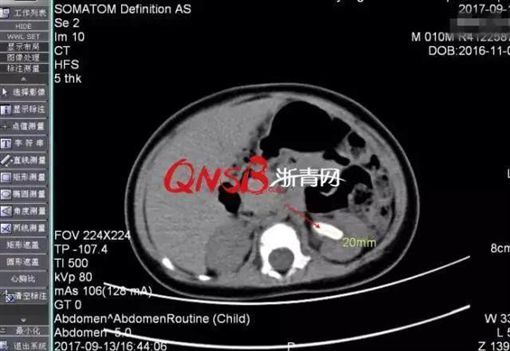

▼10月大男嬰尿布包太緊引發腎結石。(圖/翻攝自浙青網)

小男嬰的父親表示,兒子於今年八月中開始發燒,最高曾燒到40°C,因為正值炎夏,家人也沒有特別在意。後來他帶兒子到醫院求診,才意外發現兒子左腎有一顆直徑2公分左右的結石,而發燒的緣由正是因為尿道感染。

根據陸媒報導,小男嬰左邊腎臟了有一顆直徑約兩公分的「感染性結石」,還出現腎積水、輸尿管擴張等情況。醫生坦言:「這對於幾個月大的嬰兒來說,應該說是巨石了」。小男嬰的父親無奈的說,「當時真的驚呆了,出生才10個月的孩子身體內怎會有大結石?」

▼小男嬰尿布包太緊引發腎結石。(圖/翻攝自浙青網)